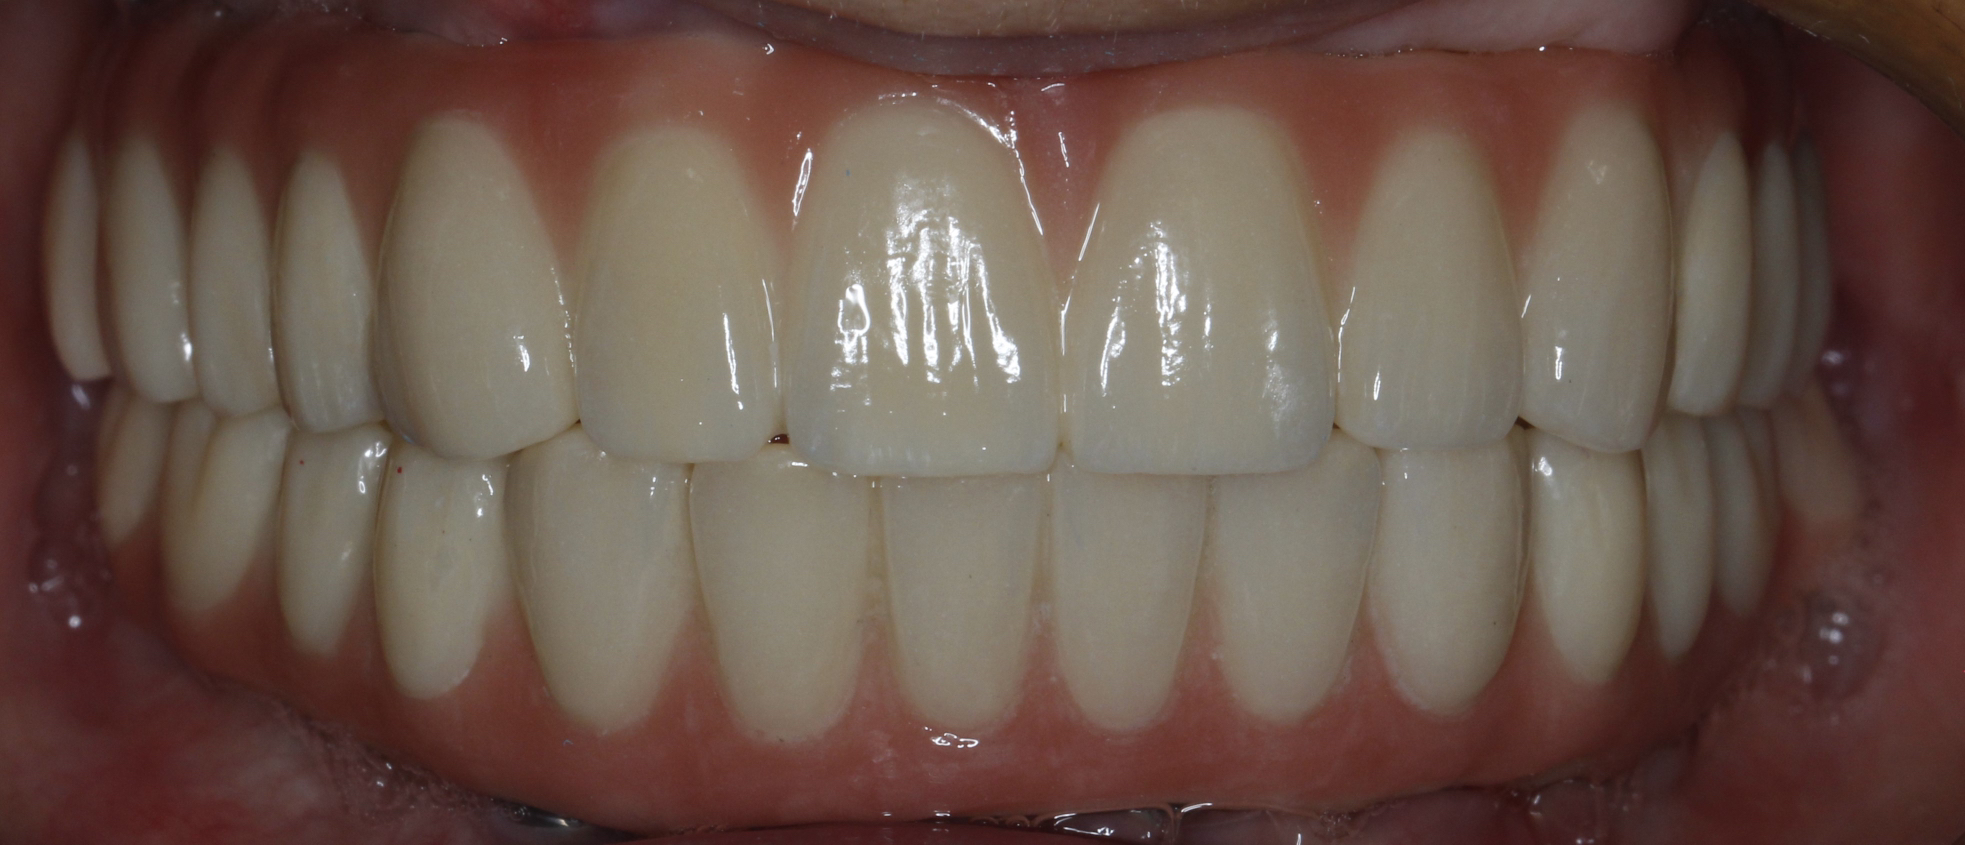

该患者就是因牙周病导致牙齿松动脱落,我们通过在全口牙槽骨上植入16颗种植体,然后在种植体上安装连桥牙冠,从而恢复半口牙齿的咀嚼功能和美观。相对于传统的种植修复方式缺一颗种一颗。4-8颗种植体的种植手术创伤相对较小,大大的减少了患者的疼痛感。

种植牙是当前缺牙修复的理想选择,但成功与否依赖医生技术、患者自身条件和术后维护。尽早修复缺牙,才能避免邻牙倾斜、咬合紊乱等问题,重获健康笑容。